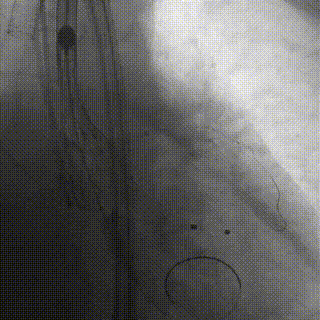

术中操作

冠脉处理前

冠脉处理后

球囊预扩

瓣膜释放

释放完成